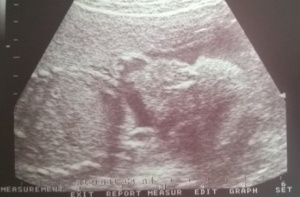

Szóval cseppet sem pihentetőek az éjszakáim. Sem. Hogy nappal pörögni kell velük, azt már megszoktam. De hogy még éjjel is... Legújabb, hogy már hiába vagyok fáradt, egyszerűen nem tudok elaludni. Hiába jön el a megváltó este 9 óra,miután elcsitítottam a gyermekeim és szép csendben kiülök a levegőre és csak pillogok a csillagokra. Erőm az már nincs semmilyen értelmes tevékenységre. Jaaj ,nagyon számolom már visszafele az időt. Még pár ultrahang, vérvizsgálat, ctg és már a finishben is leszek. Azért jó, hogy vannak ez a vizsgálati időpontok, amiket lehet várni, kicsit lehet bele kapaszkodni, így talán mégsem tűnik olyan rettenetesen hosszúnak a vége. Jut eszembe, kicsit feldobtam ezt a hosszú várandósságot és elmentem kismamafotózásra. Már régóta szerettem volna, most sikerült végre. Képeket a következő naplóban hozok, remélem addigra elkészülnek!